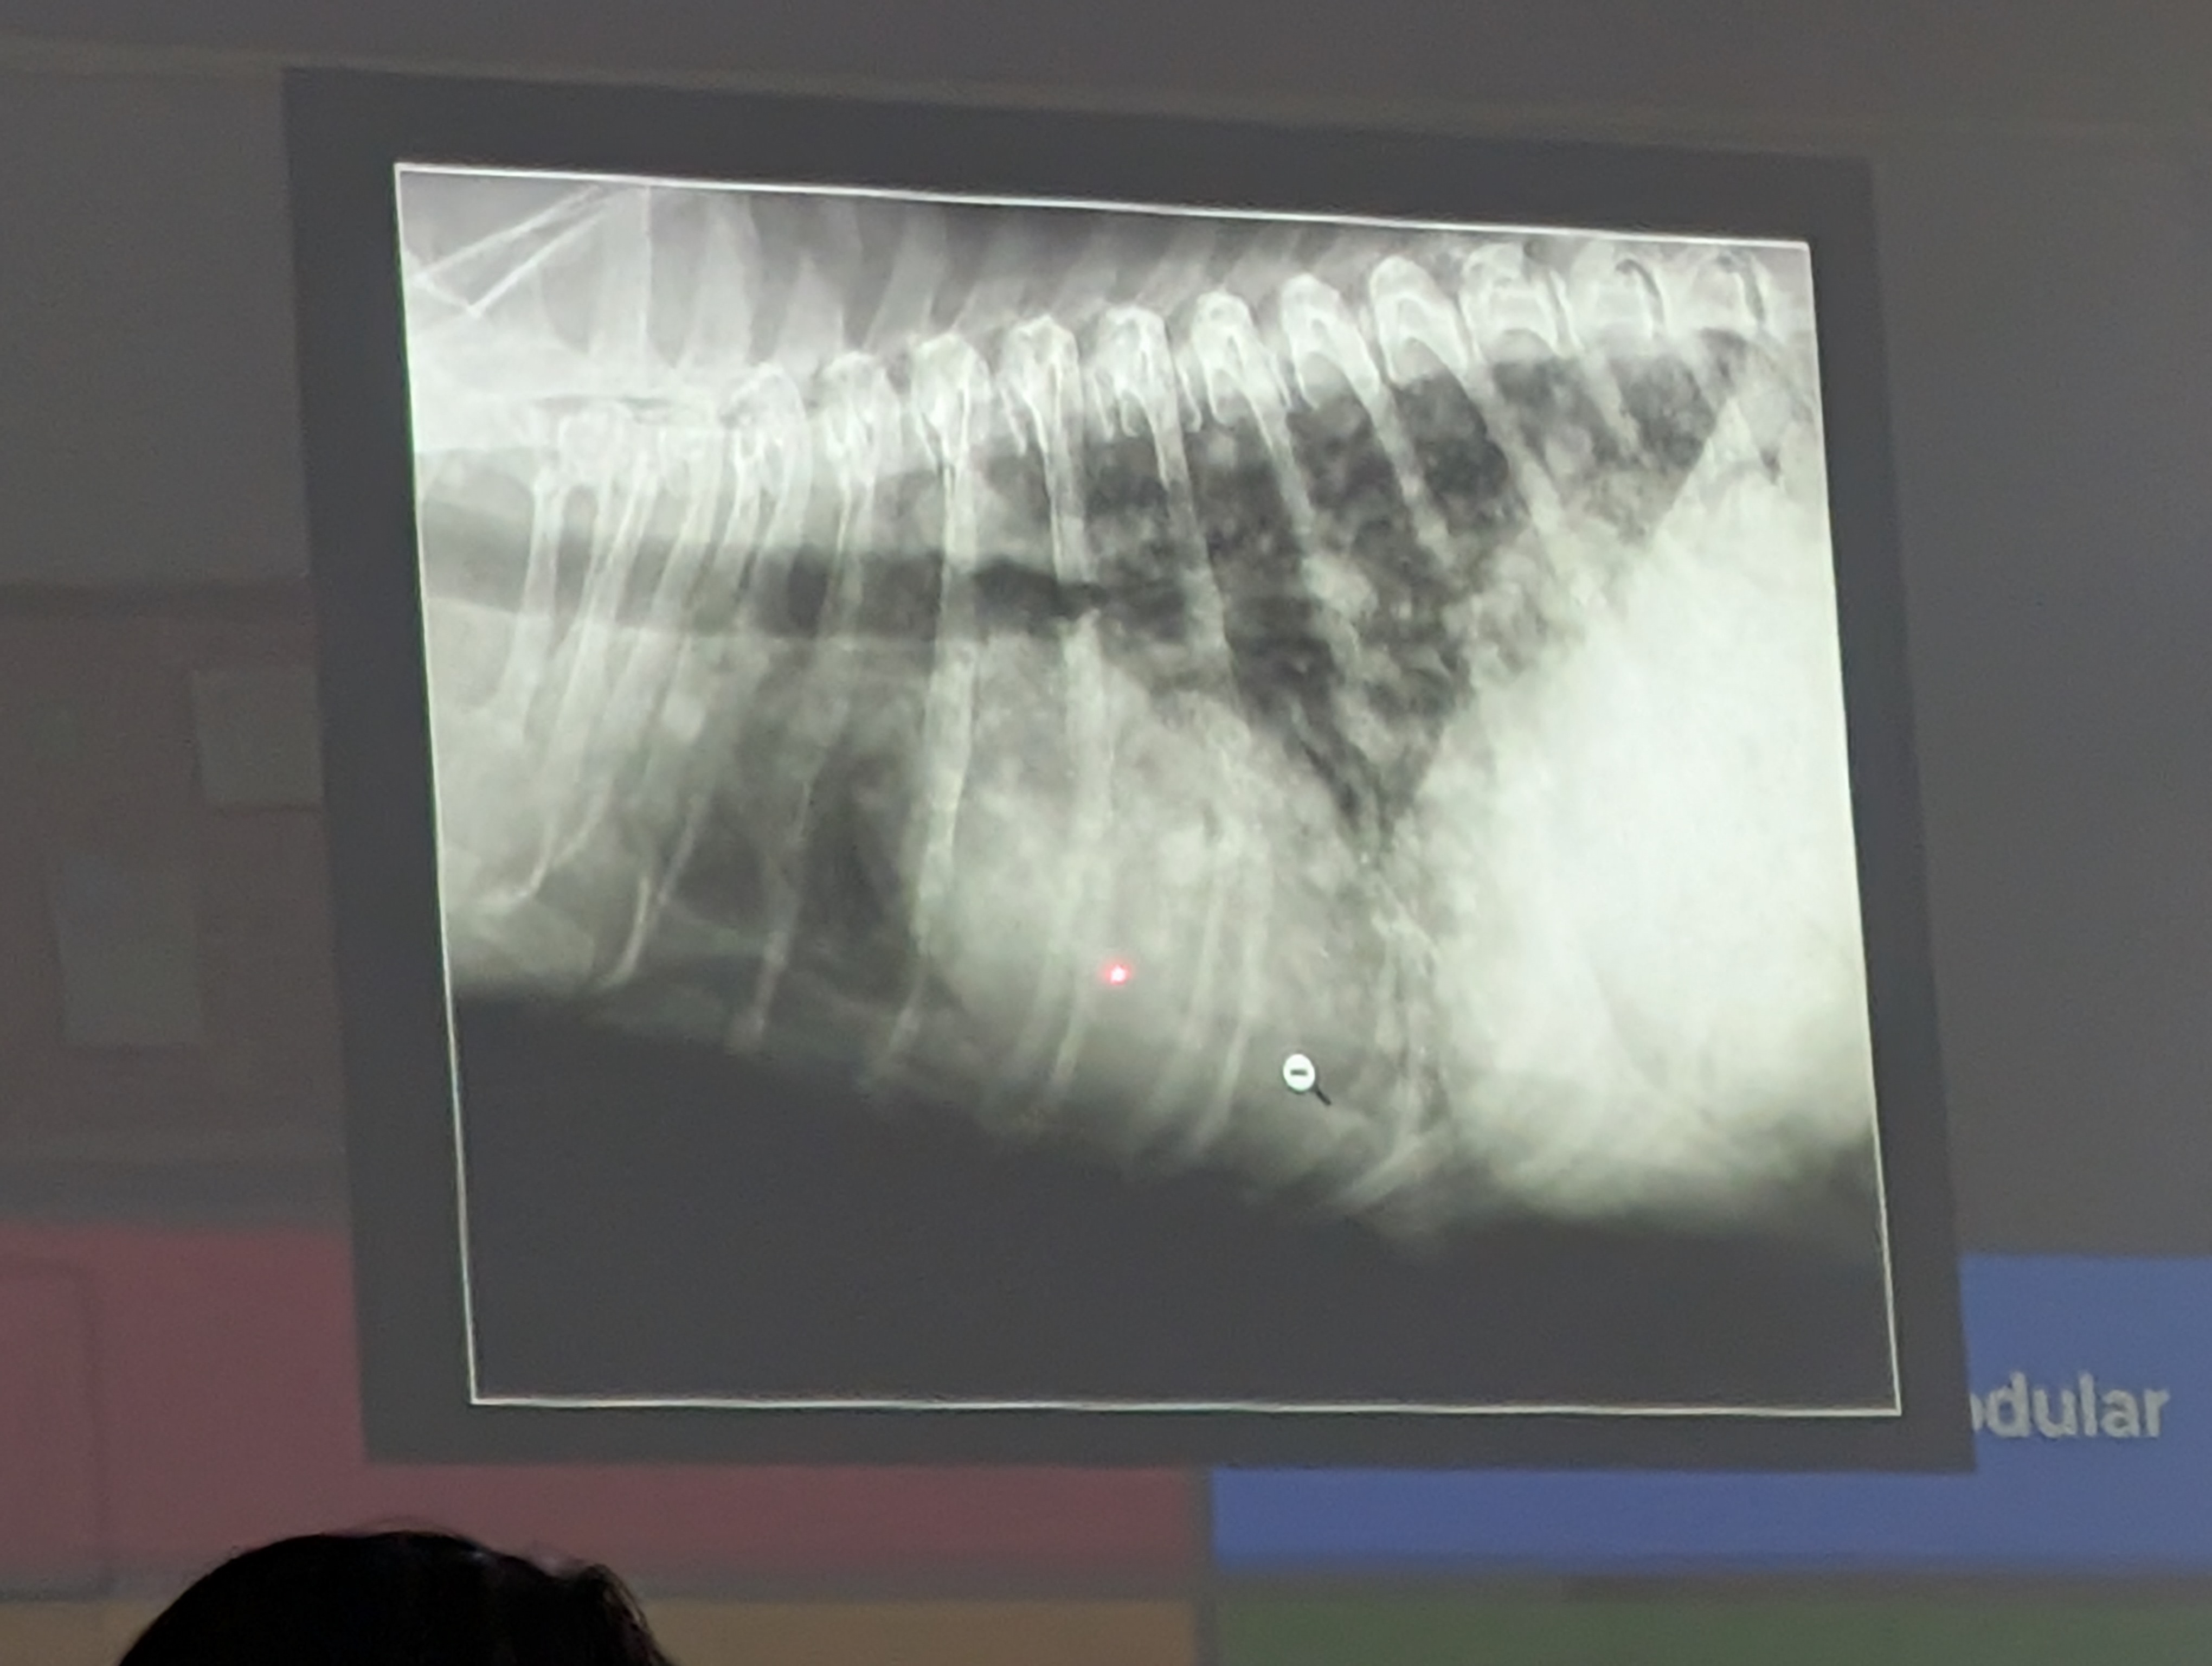

Preguna 7 - Multiple respuesta

- Hay efusion pleural

- Hay Hipertensión pulmonar (dilatación y tortuosidad de las arterias pulmonares, una prominencia del tronco pulmonar y un aumento del tamaño de las cavidades derechas del corazón. En este caso se ve porque si lo comparamos con la 9a costilla vemos que es mucho mas gruesa la arteria de la derecha que la costilla)